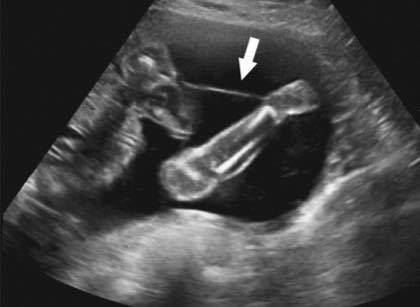

確定發現是因為羊膜帶症候群所以導致肢體缺損

有時候當胎兒活動的時候這些帶狀物就會糾纏到胎兒的身上

會影響到血流供給造成胎兒的生長缺陷

最常見的就是肢體的缺陷

羊膜帶症候群(amniotic band syndrome)

圖來自UC Davis Health ![]()